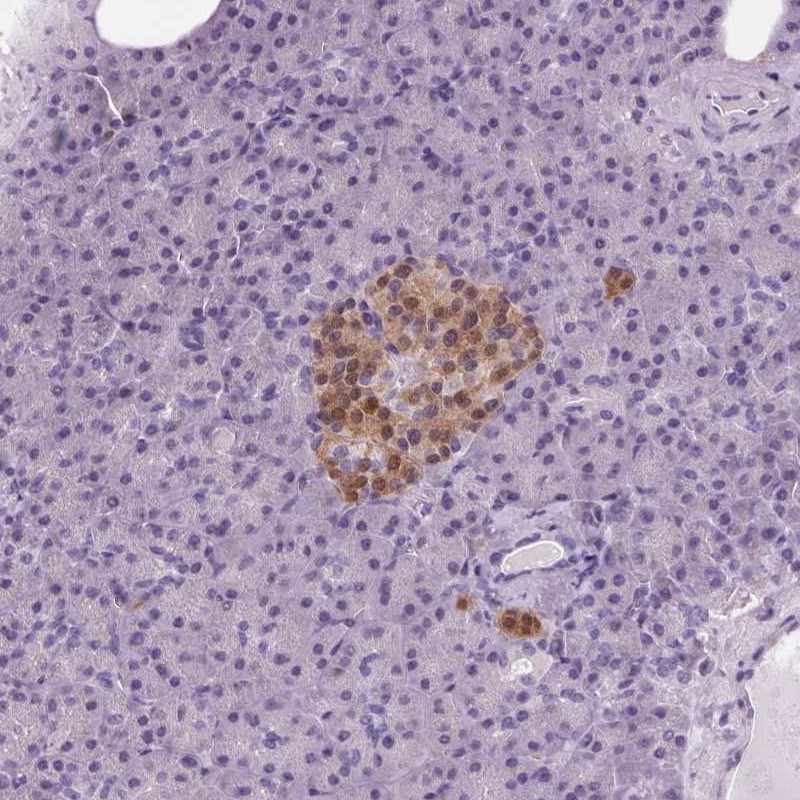

Immunohistochemical staining of human pancreas shows cytoplasmic and nuclear positivity in islets of Langerhans.